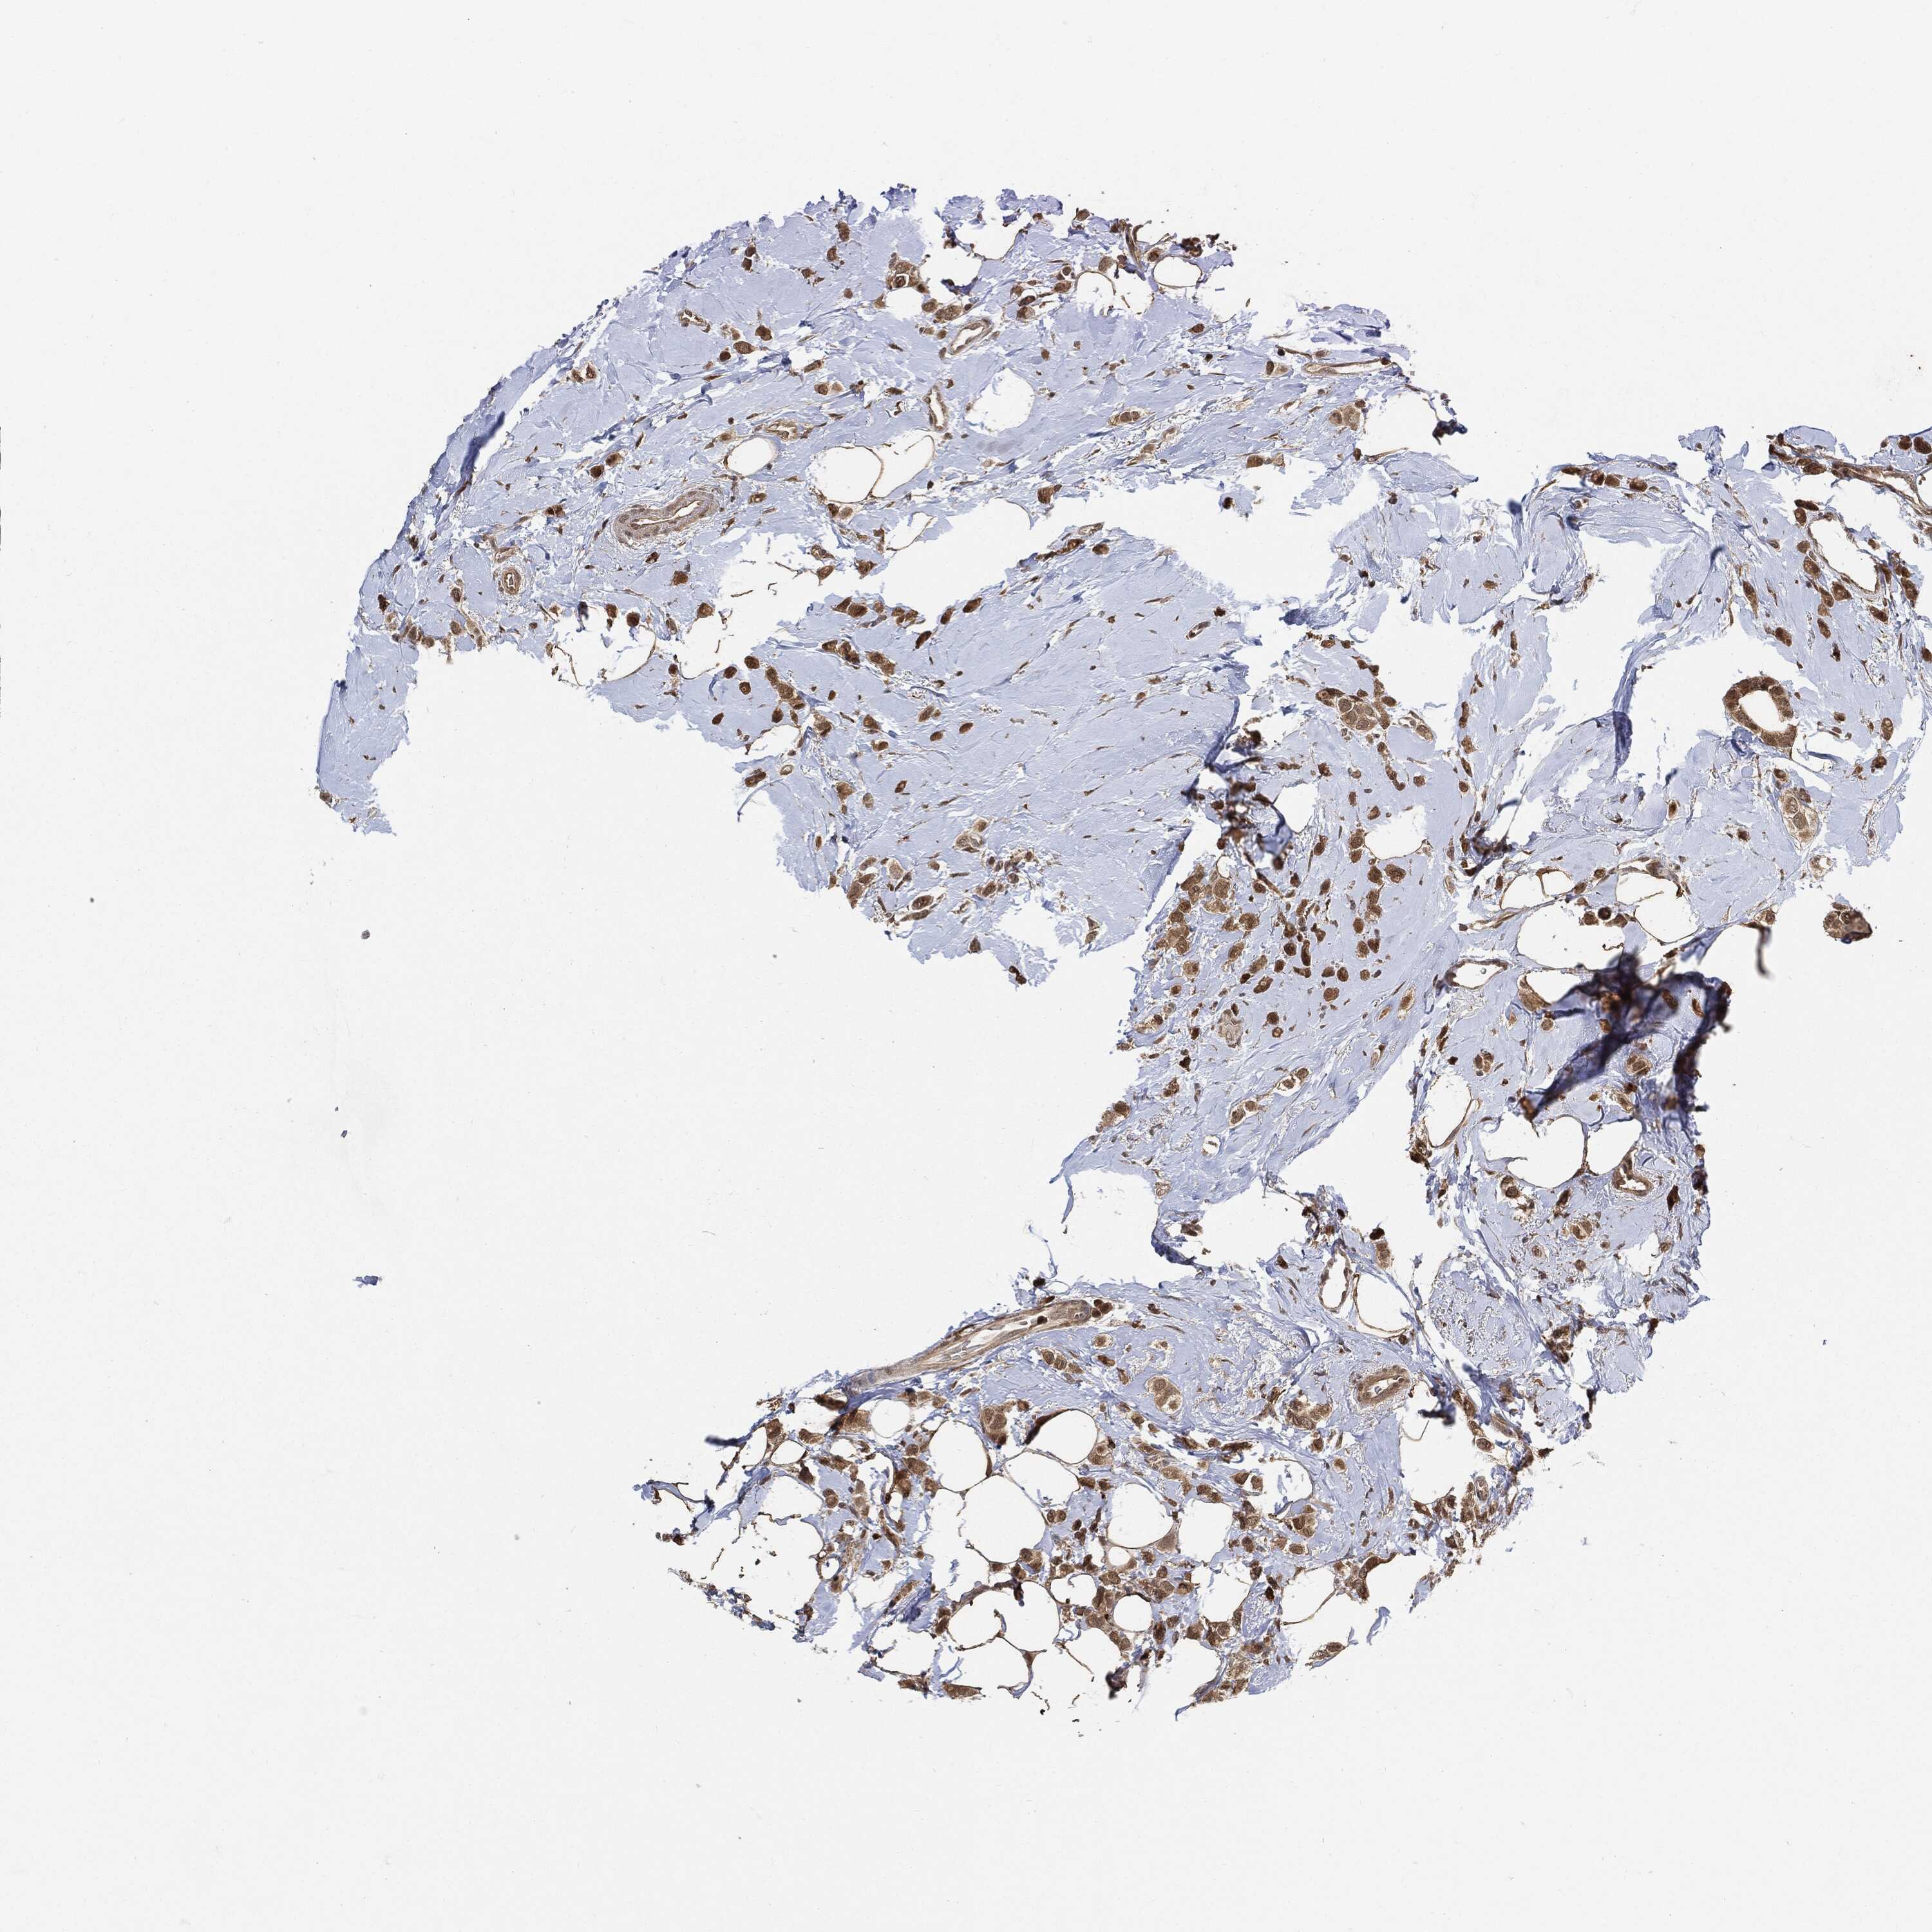

BRCA TCGA BRCA VALIDATION PROTEIN EXPRESSION

ANTIBODIES

AND

VALIDATION